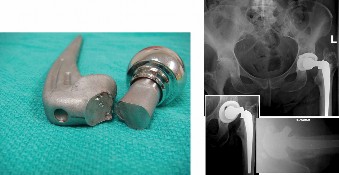

An 82-year-old woman, with a BMI of 33.9 and history of total hip replacement performed 8 years ago, sustaine…

A 51-year-old male presents with a chief complaint of left hip pain that has been progressively worsening for…